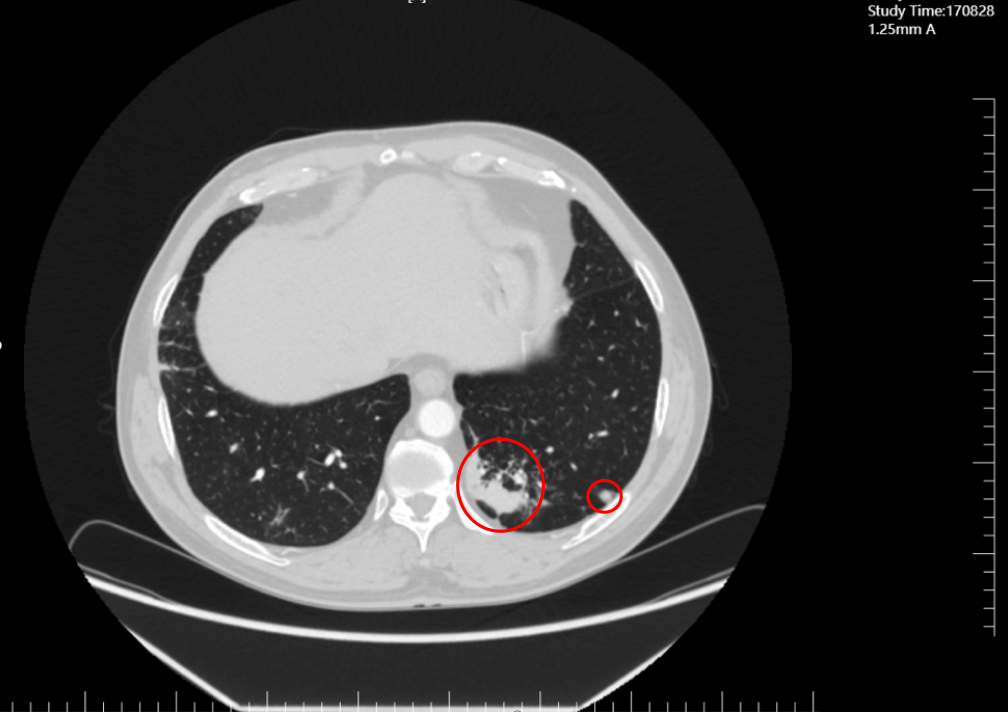

2023年5月,肖先生被确诊为左肺鳞癌T3NxM1 Ⅳ期(晚期),肿瘤已出现远处转移,传统治疗手段难以实现长生存。

同年7月,患者转入我院肿瘤科,科室团队立即启动“多学科诊疗思维+个体化精准评估”流程。

治疗期间依托科室影像诊断技术(高分辨率CT)、实验室检测技术(肿瘤标志物动态监测),建立“周度评估+月度复查”的技术监测体系:

2023年11月(联合治疗5周期),CT显示肺部原病灶大部分退缩为磨玻璃影,技术层面验证“肿瘤活性显著降低”;